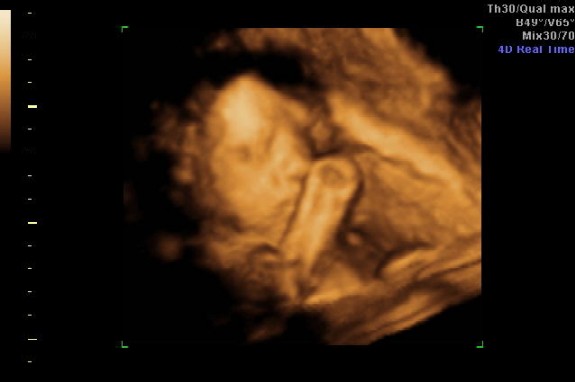

Azt mondta az UH-n a doki, hogy anatómiailag nagyon rendben vannak a babák, de nem túl fotógének és ez igazis. Felteszem a képeket, de nem nagyon látszik semmi.

Ja mindketten fejjel lefelé vannak most épp. Anna 870 g, Zalán 920 g, akkora egyikük mintha csak 1 gyermek lenne a pocimban.

Ja a két felső képen Anna látható az alsókon Zalán.